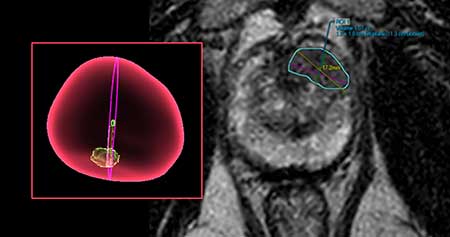

- Prostate MRI targeted biopsy: Uses state-of-the-art technology that allows the MRI images and real-time ultrasound images to be fused for a prostate MRI targeted biopsy with improved accuracy.